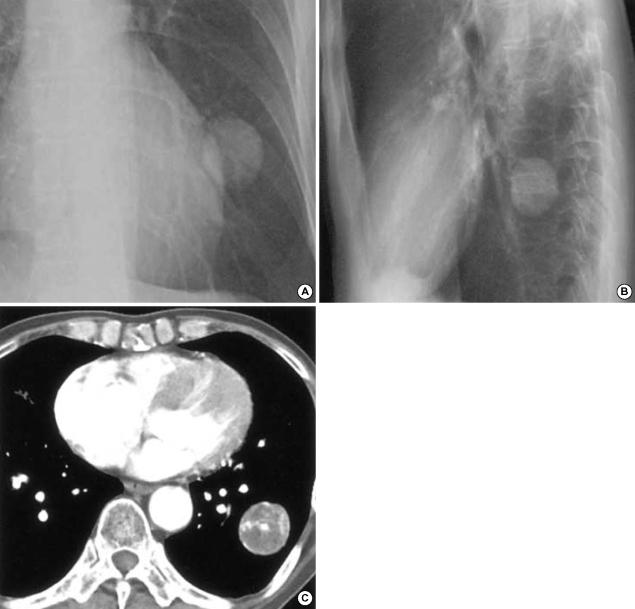

Extraskeletal Ewing's sarcoma (EES) is a branch of neuroectodermal tumor (PNET), which is very rare soft tissue sarcoma. We report a case of EES/PNET arising is the lung of a 67-yr-old man. Computed tomography, bone scintigraphy, and positron emission tomography confirmed the mass to have a primary pulmonary origin. The mass showed positive reactivity in the Periodic Acid Schiff (PAS) stain and MIC-2 immunoreactivity in immunohistochemical stain. Fluorescence in situ hybridization (FISH) was performed, which revealed an EWSR1 (Ewing sarcoma breakpoint region 1) 22q12 rearrangement. The diagnosis was confirmed both pathologically and genetically. The mass lesion was resected, and the patient is currently undergoing chemotherapy.

骨外尤文肉瘤(EES)是神经外胚层肿瘤(PNET)的一个分支,是一种非常罕见的软组织肉瘤。我们报告一例发生于一名67岁男性肺部的EES/PNET病例。计算机断层扫描、骨闪烁显像和正电子发射断层扫描证实该肿块起源于肺部。该肿块在高碘酸希夫(PAS)染色中呈阳性反应,在免疫组织化学染色中呈MIC-2免疫反应性。进行了荧光原位杂交(FISH),结果显示存在EWSR1(尤文肉瘤断点区域1)22q12重排。病理和基因诊断均得到证实。切除了肿块病变,患者目前正在接受化疗。